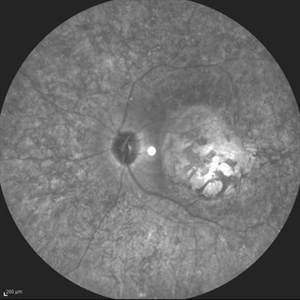

Best Disease Best DiseaseMar 9 2013 by Hamid Ahmadieh, MD Autofluorescence Imaging of the left eye of a 49-year-old man with decreased VA due to advanced Best disease. Photographer: Soodabeh Fooladin, Negah Eye Center, Tehran Imaging device: Heidelberg Spectralis Condition/keywords: autofluorescence imaging, Best disease